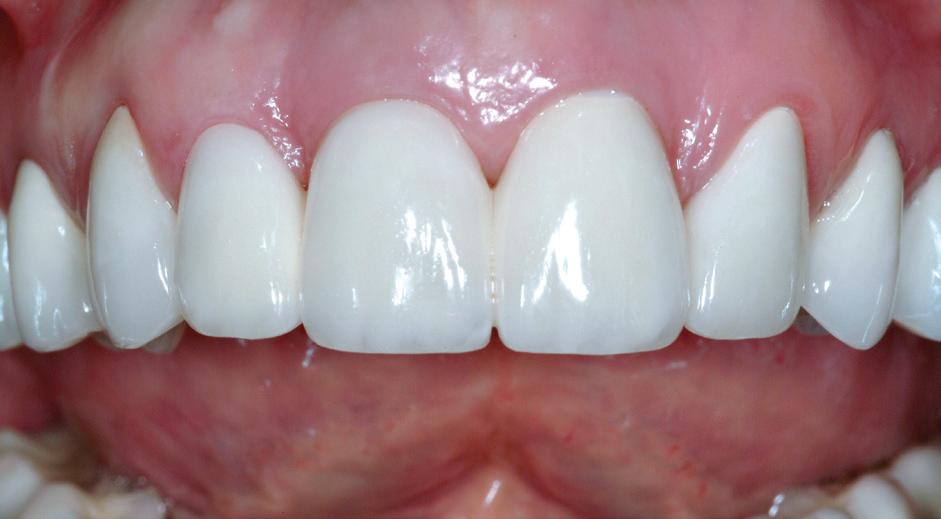

izolarea cu digă de cauciuc, restaurarea din amalgam a fost îndepărtată complet și s-a obținut accesul la cavitatea carioasă (fig. 3-5). În ciuda proximității față de țesutul pulpar, nu a avut loc nicio expunere, iar cavitatea de clasa a II-a a fost restaurată complet cu Biodentine™ (fig. 6-8).

La controlul de două luni, nu au fost raportate simptome, nu s-a obiectivat radiologic nicio leziune periapicală, iar examenul clinic a

demonstrat o vitalitate în limite normale (fig. 9-10). Prin urmare, s-a decis efectuarea restaurării definitive, păstrând Biodentine™ ca bază definitivă.

Materialul Biodentine™ a fost parțial îndepărtat și peste acesta s-a plasat o obturație din compozit (fig. 11). S-a efectuat o gravare selectivă a smalțului, urmată de aplicarea unui sistem adeziv (Palfique Bond®, Tokuyama) (fig. 12-13). După foto-

polimerizare, s-a fixat sistemul de matrice (SeptoMatrix, Septodont) și s-a utilizat o matrice mare cu un inel moale pentru un contur mai bun și un punct de contact proximal (fig. 14). Restaurarea a fost începută în porțiunea distală, transformând cavitatea de clasa a II-a într-o cavitate de clasa I (fig. 15). În final, suprafața ocluzală a fost restaurată folosind compozitul Palfique LX5® (Tokuyama) (fig. 16). După fotopolimerizare, s-a aplicat gel de glicerină pentru a permite o mai bună fotoactivare a stratului superficial. Restaurarea a fost apoi finisată și lustruită, înainte de îndepărtarea digii de cauciuc și verificarea ocluziei (fig. 17).

Figurile:

6. Biodentine™ aplicat prin procedura

Bio Bulk-Fill. 7. Situația clinică după 12 minute și îndepărtarea matricii.

8. Situația clinică după îndepărtarea digii de cauciuc. 9. Radiografia de control la 2 luni postoperator.

10. Restaurarea Biodentine™ după 2 luni.

11. Îndepărtarea părții externe a Biodentine™.

12. Gravarea selectivă a smalțului.

13. Aplicarea adezivului.

14. Plasarea unui sistem de matrice (Septomatrix, Septodont)

15. Reconstrucția cu compozit a peretelui distal.

16. Restaurarea imediat după finalizare.

17. Situația clinică după finisare și lustruire.